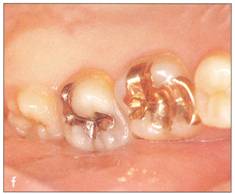

Fi 545e45f g 5-7c Recipient site prior to treatment. The patient visited the clinic because of root fracture of the maxillary right lateral incisor in the cervical area. |

Fi 545e45f g 5-7d Removal of fractured fragment. The tooth was extracted because little root length remained. |

Fi 545e45f g 5-7e Two weeks after extraction ofthe lateral incisor and just before transplantation. |

Fi 545e45f g 5-7f Preoperative view of the donor tooth. |

Fi 545e45f g 5-79 The extracted donor tooth. |

Fi 545e45f gs 5.7h and 5-7i After transplantation of the donor tooth. |

Fi 545e45f g 5.7j Two weeks after transplantation. The root canal has been cleaned and filled with calcium hydroxide. |

Fi 545e45f g 5-7k Three months after transplantation. The calcium hydroxide is being replaced with gutta percha. |

Fi 545e45f g 5-71 Three months after transplanta. tion. Notice the dark appearance of the crown. |

Fi 545e45f g 5-7m After bleaching of the transplant. ed tooth. |

Fi 545e45f gs 5-7n and 5-70 Composite resin res. toration of the transplanted tooth. |

Fi 545e45f g 5-7p Fi 545e45f ve months after transplantation. |

Fi 545e45f g 5-7q Three years after transplantation. |